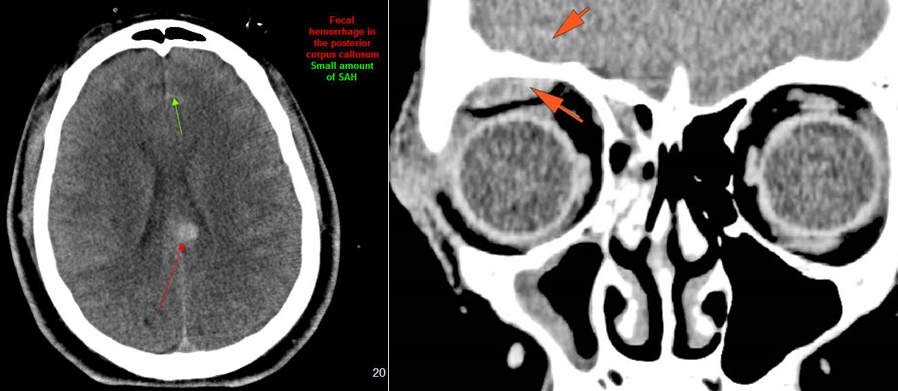

There is subperiosteal, epidural or subdural hematoma and/or pneumocephalus along the boney walls of the anterior or middle cranial fossa or elsewhere. |

No | NA |

There is subarachnoid bleeding. |

There is evidence of parenchymal brain injury . |

Unstable upper cervical spine and possible craniocervical junction injury, possible vertebral artery injuries associated with a complex mandibular fracture/dislocation.

Cervical MRI to be done immediately and CT angiography of the neck considered.

Emergent (Action Necessary now)